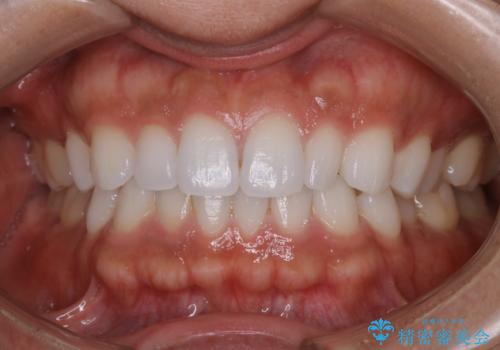

歯のメンテナンス

治療症例の内容

- しばらく歯科でのクリーニングをしていないため、きれいにしたいとのことでした。

PMTC30分コースを行いました。